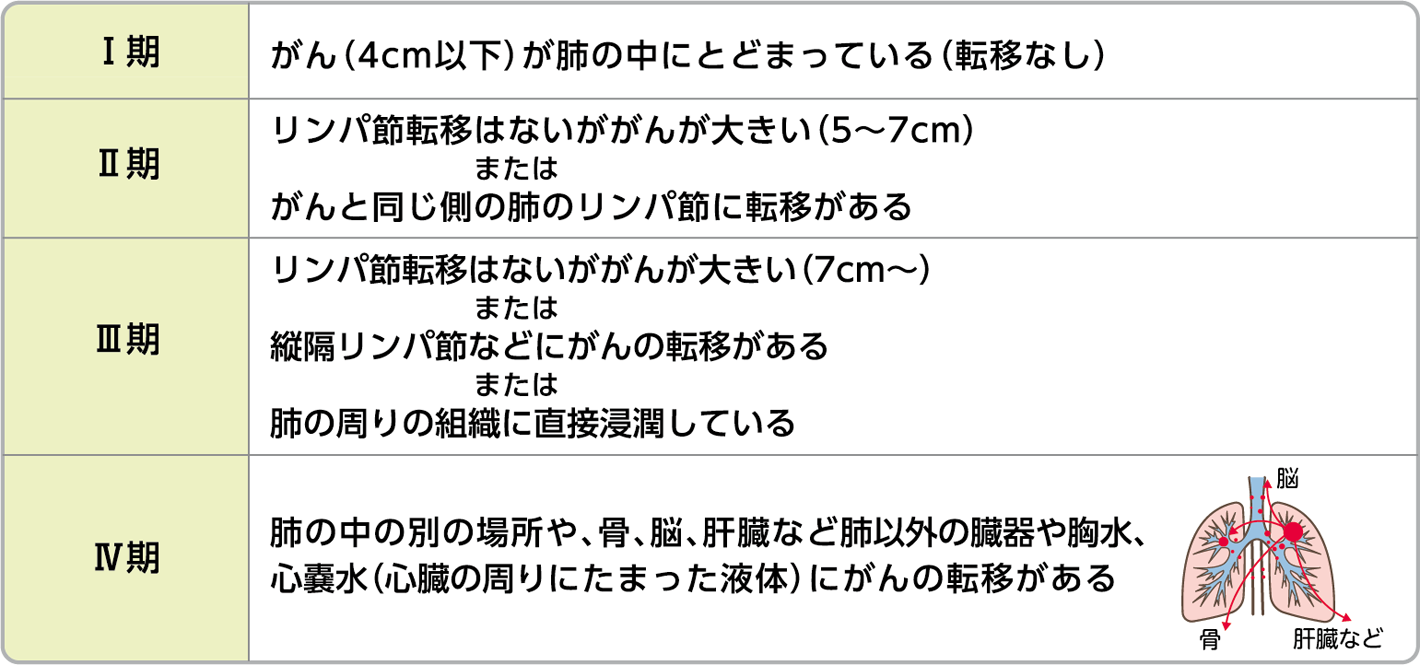

NSCLCは 0 から 4 に分類されます。数値が低い場合は、がんがそれほど遠くまで広がっていないことを意味します。

ステージ 1 の肺がんでは、原発 (元の) 腫瘍は 4 センチメートル (cm) 以下です。さらに、がん細胞はリンパ節や体の離れた部分(他の臓器など)には広がっていません。